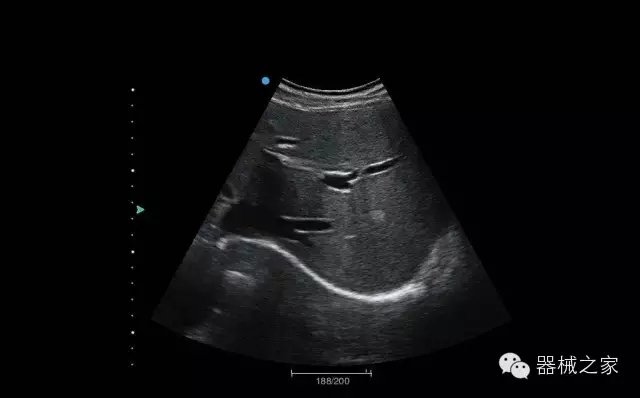

睪丸低速血流

臍帶血流

頸動(dòng)脈頻譜